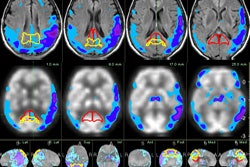

The license was provided for remote diagnostic viewing of CT, PET, MRI, and SPECT images on the Apple iPhone, iPod Touch, and iPad. The software is now available on the Canadian App Store, according to the company.